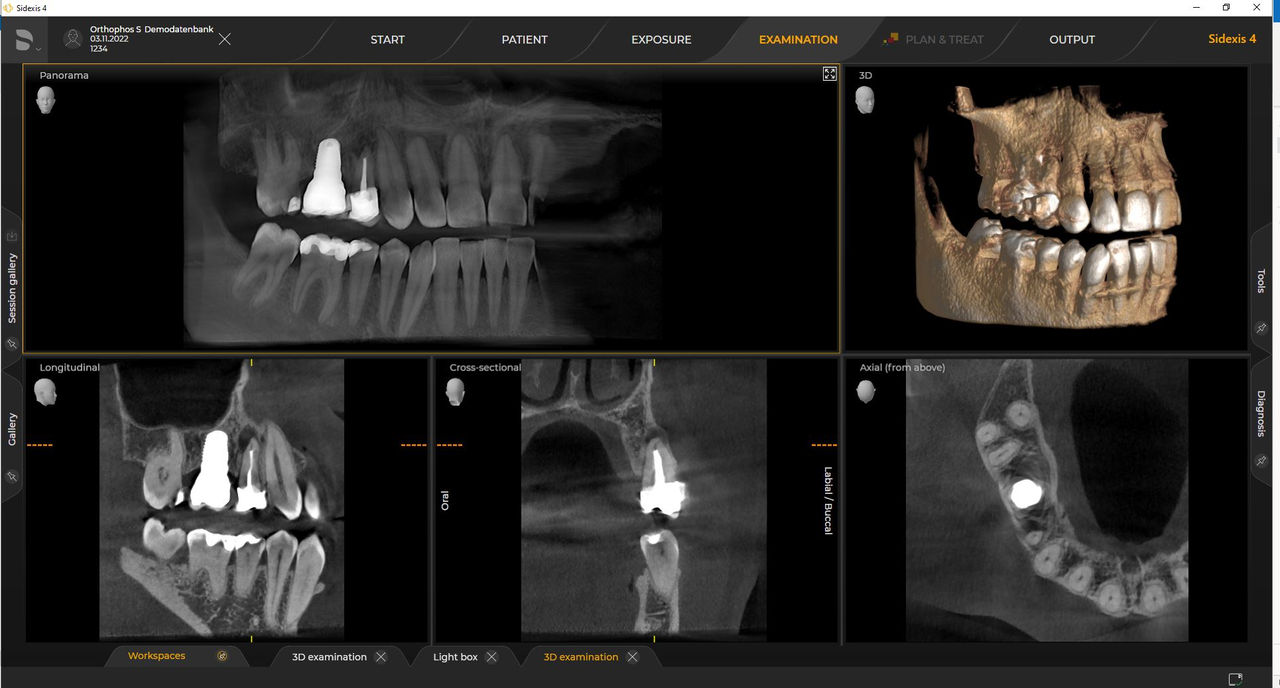

Das hochwertige 2D/3D-Röntgengerät mit umfassendem Leistungsspektrum für jede Praxis. Ob als reines 2D-Gerät oder mit integriertem 3D-Modul – Orthophos S ist ein zuverlässiger Partner und optimiert für alltägliche Aufgaben. Gestochen scharfe Aufnahmen dank CsI-Plus-Sensor und Autofokus. Die automatische Patientenpositionierung zusammen mit dem patentierten Okklusalaufbiss ermöglicht eine einfache und zeitsparende Patientenpositionierung. Für den Einsatz in der Kieferorthopädie ist der Orthophos S auch mit einem optionalen Ceph-Arm erhältlich. Und da Zukunftssicherheit für Dentsply Sirona wichtig ist, kann der Fernröntgenausleger jederzeit nachgerüstet werden.

Von Ø 5 cm x 5,5 cm bis Ø 8 cm x 8 cm oder optional bis Ø 11 cm x 10 cm

Mit dem Intelligent Low Dose-Modus erhalten Sie 3D-Röntgenbilder im Dosisbereich einer 2D-Röntgenaufnahme. Im HD-Modus werden während eines einzelnen Umlaufs bis zu 1.400 Einzelbilder aufgenommen und zu einem 3D-Volumen mit bis zu 80 μm zusammengeführt. Der Vorteil für Sie: rauschärmere Aufnahmen in hoher Auflösung.

Ein breites Spektrum an Volumengrößen für verschiedene diagnostische und klinische Anforderungen von Ø 5 x 5,5 cm bis Ø 11 x 10 cm